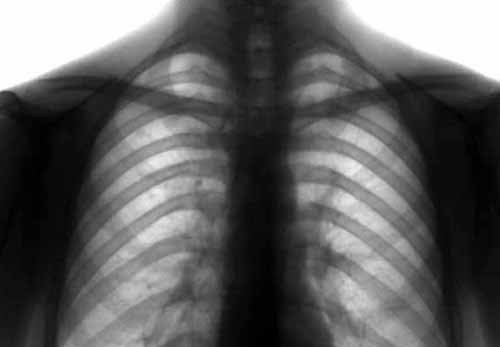

В Украине стартовала неделя борьбы с туберкулёзом

В Украине — эпидемия туберкулеза. По имеющимся данным, на учёте состоят около миллиона больных. Ежегодно регистрируют около 160 тыс. случаев новой открытой формы туберкулёза.